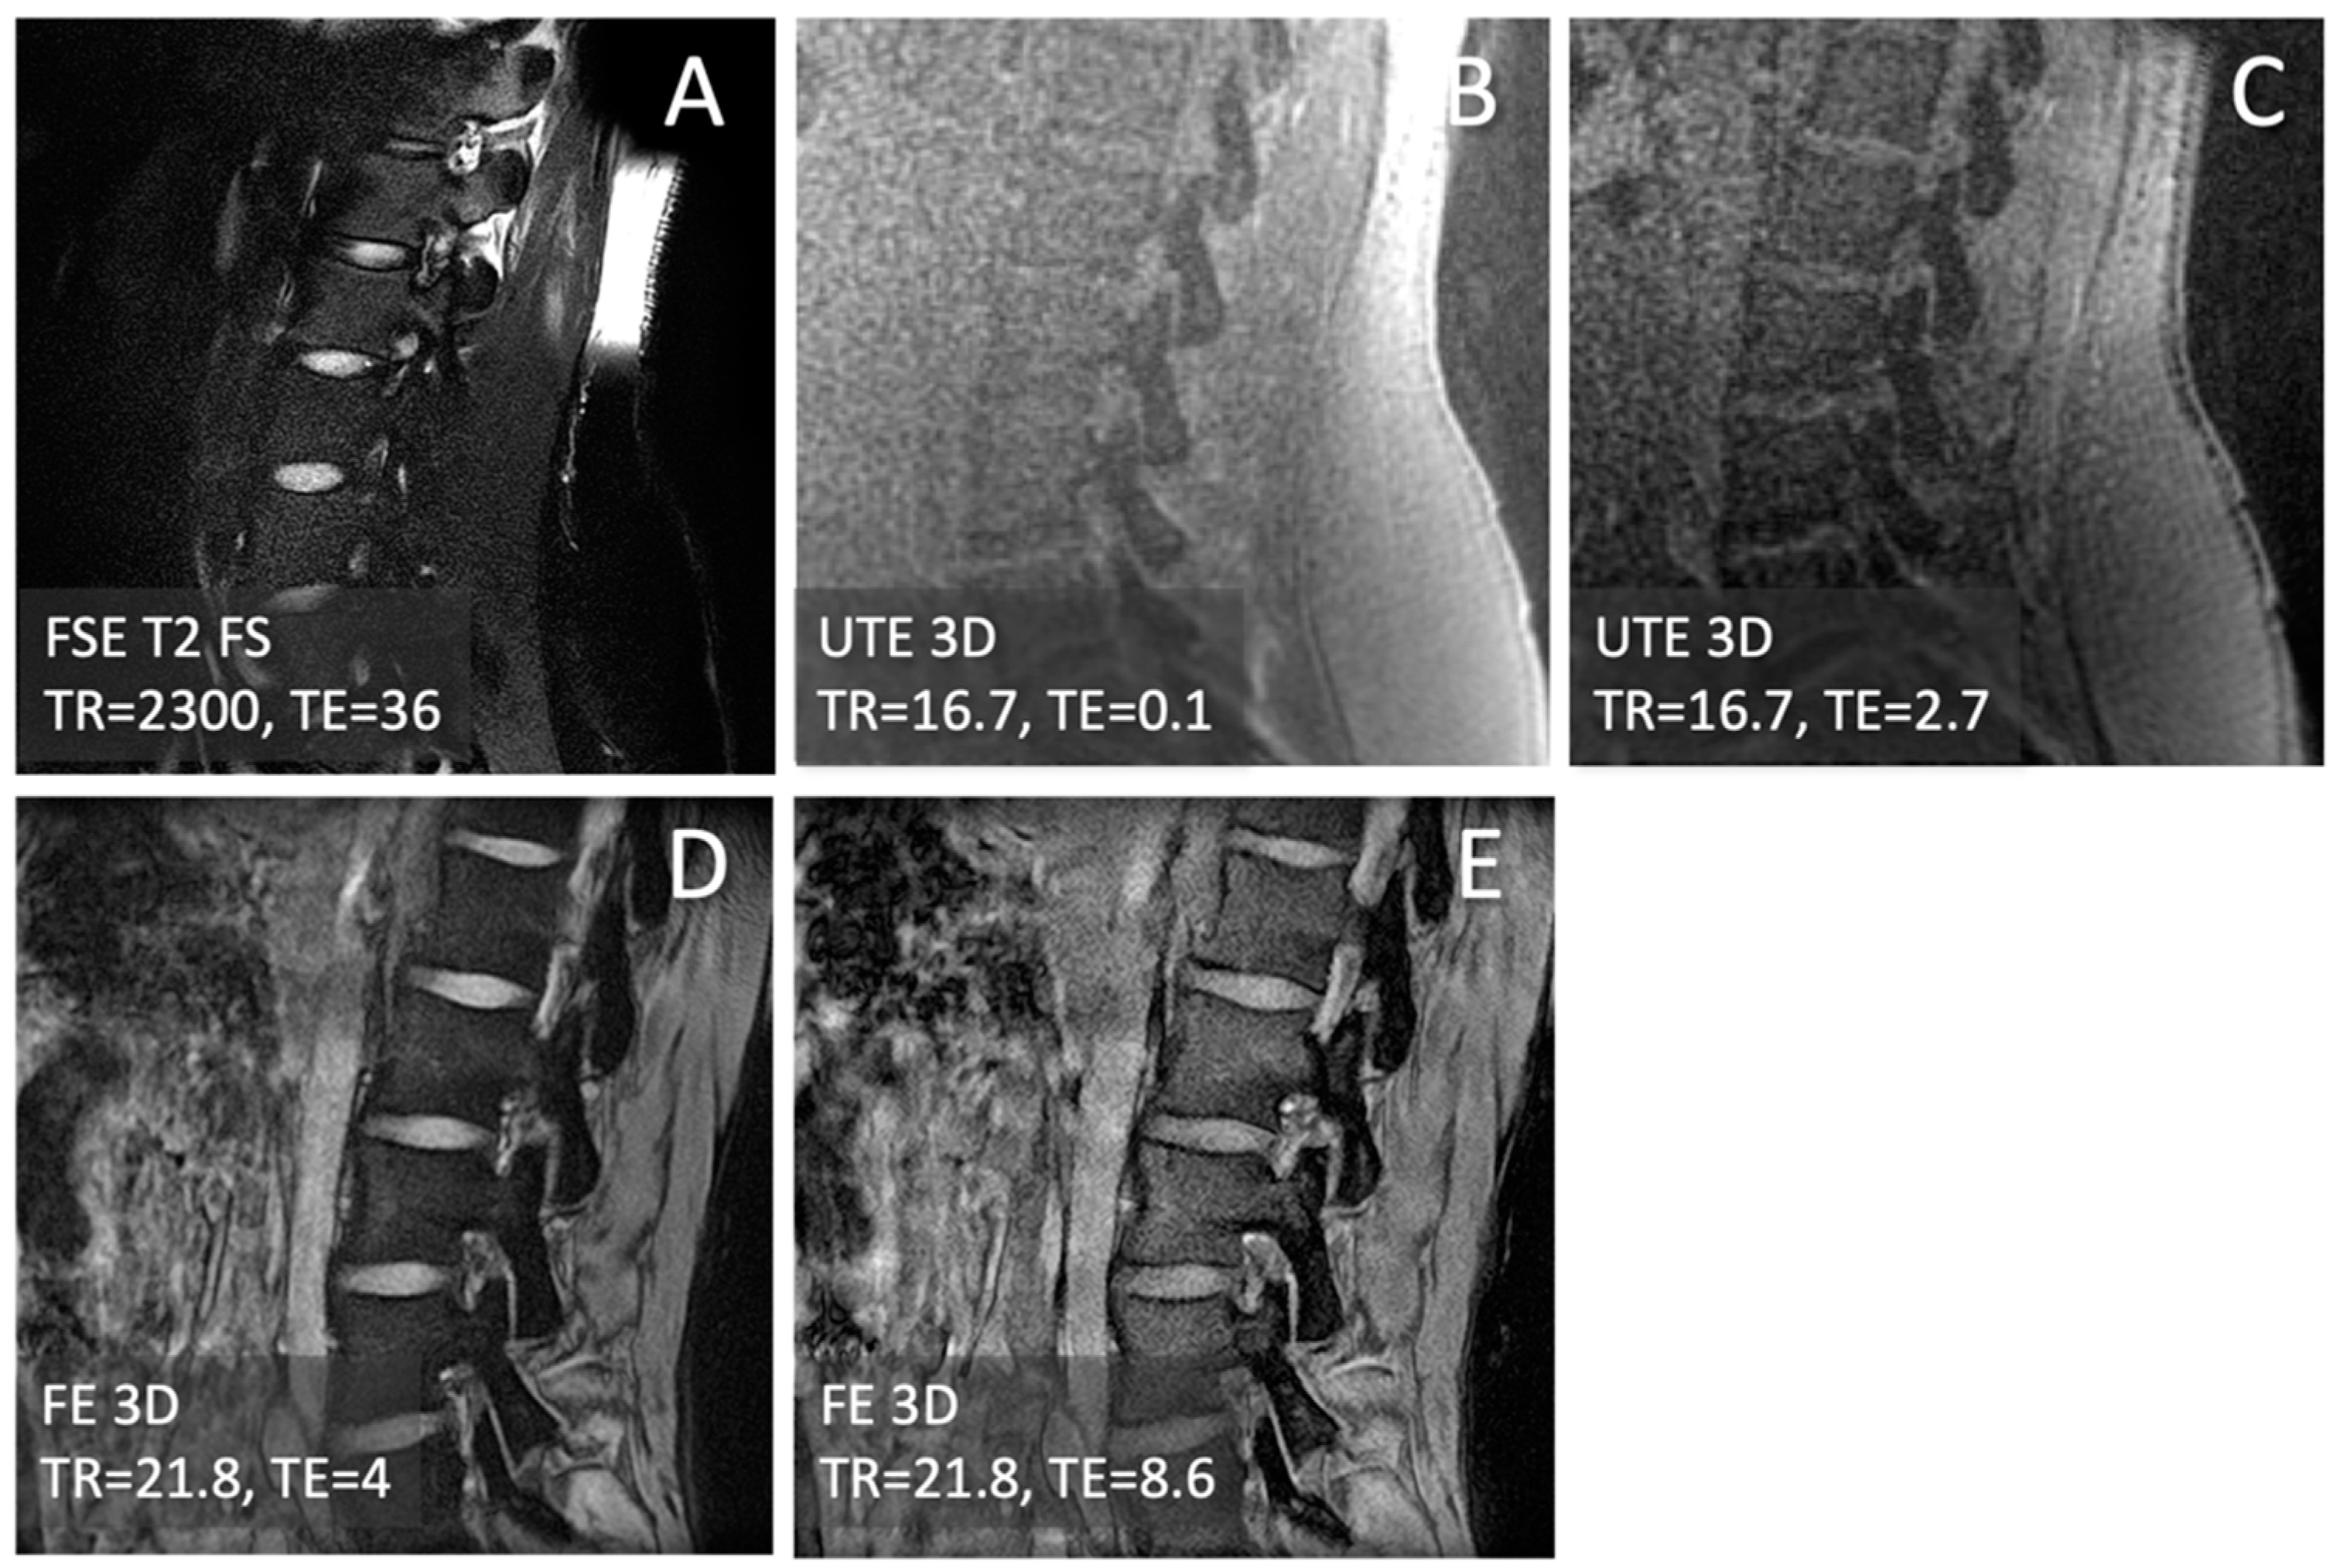

2.2. MRI

2.3. CT-like Image Processing

3.1. Observations